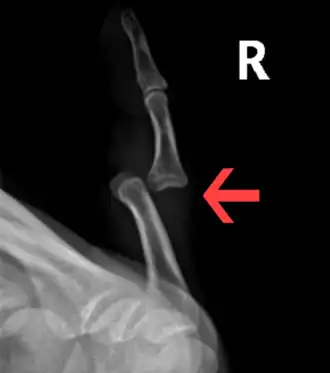

-

Dislocation of the left index finger -

Radiograph of right fifth phalanx bone dislocation -

Radiograph of left index finger dislocation